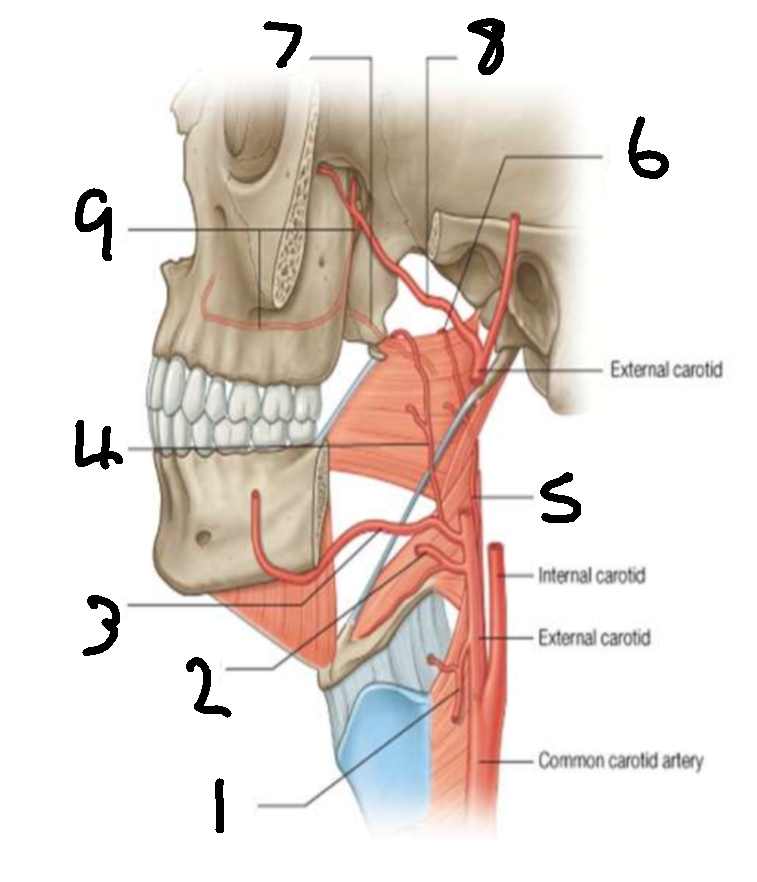

What is 1?

superior thyroid artery

What is 2?

lingual artery

What is 3?

facial artery

What is 4?

ascending palatine artery

What is 5?

ascending pharyngeal artery

What is 6?

palatine branch of pharyngeal artery

What is 7?

lesser palatine artery

What is 8?

maxillary artery

What is 9?

greater palatine artery